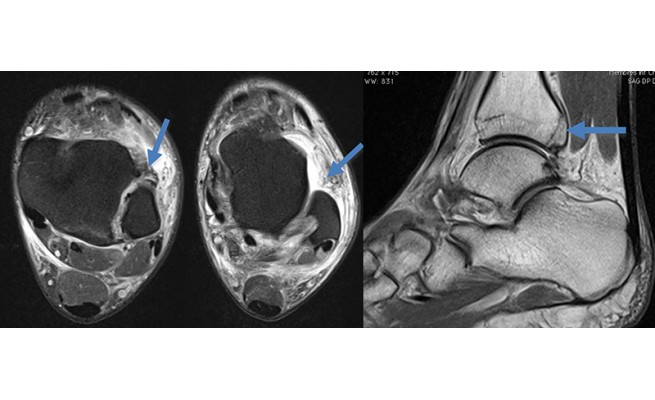

Entorse de la syndesmose tibio-fibulaire inférieure

Les lésions de la syndesmose tibio-fibulaire sont rares, totalisant 6 % des entorses de la cheville. Le diagnostic peut être difficile et est souvent assimilé à une entorse de la cheville. Ces lésions doivent être considérées chez les athlètes présentant des douleurs ou un traumatisme en torsion de la cheville.